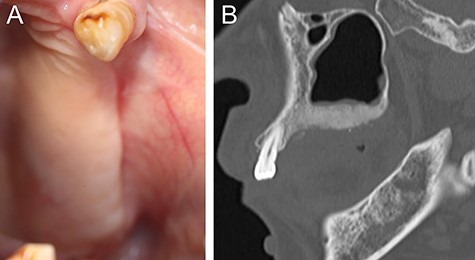

A 69-year-old woman was referred to our hospital by a dentist at another hospital because of swelling in her left maxilla. There was the mobility of the left maxillary second premolar and first molar (FDI #25 and #26) and swelling of the surrounding gingiva. Computed tomography (CT) images revealed maxillary bone expansion with a ground glass appearance (Fig. 1). The patient had begun steroid therapy for polymyalgia rheumatica 4.5 years earlier. Since then she had been taking alendronate, one of the oral BPs, for the prevention of glucocorticoid-induced osteoporosis.

(A) Intraoral photograph showing gingival fistulas in #25 and #26 extraction sites (arrows). (B) Sagittal section of CT image showing separated sequestrums in the left maxilla (arrow) and bone resorption in the periapical area of #24 (arrowhead).

At 1 year after the extractions, a purulent discharge and exposed bone with gingival fistulas were observed in the extraction sites (Fig. 2A). CT images revealed separated sequestrums in the left maxilla and bone resorption in the periapical area of the left maxillary first premolar (FDI #24) (Fig. 2B). With the permission of the patient’s attending physicians, the alendronate was withdrawn. After exposed bone had been observed for 8 weeks, the patient was clinically diagnosed with Stage 2 BRONJ accompanying FD of the left maxillary bone. Under general anesthesia, we first performed extraction of #24 and sequestrectomy. We then performed a partial resection of the FD because necrotic-like bone fragments were collected by curettage of the marginal bone (Fig. 3). Finally, the surgical wound was completely closed by sutures. The histopathological diagnosis was chronic osteomyelitis with FD (Fig. 4). At 2.5 years after the operation, the healing is uneventful although residual FD bone exists (Fig. 5). Although local conditions permit the resumption of alendronate, it remains discontinued at the attending physicians’ discretion.